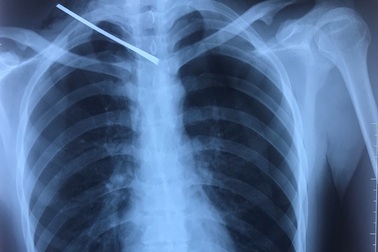

Bé trai 4 tuổi bị chiếc kim gỉ sét đâm xuyên phổiChụp X-quang bệnh nhi, các bác sĩ ở TPHCM phát hiện chiếc kim may vá quần áo đã gỉ sét nằm trong phổi trái của bé trai 4 tuổi.